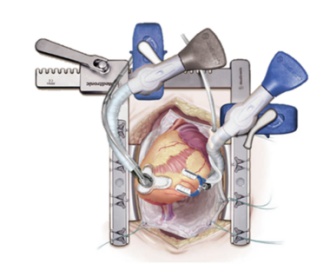

In these cases, beating heart surgery is indicated. The off-pump coronary artery bypass (OPCAB) procedure was developed in the early 1990's. In the process, stabilizers are used intraoperatively to calm the heart surface in the area of the artery to be operated on. Today, OPCAB is a gentle alternative to traditional ONPUMP surgery using a heart-lung machine and is widely used in our clinic for appropriate patients.

OPCAB-Stabilisator - Octopus-Starfish Fa.: Medtronic

OPCAB-Stabilisator - Octopus-Starfish Fa.: Medtronic